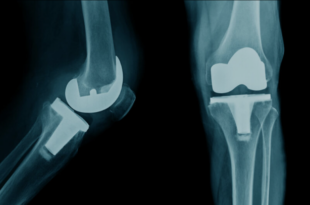

Read More »Best Knee Replacement Surgery in Jaipur: Get Trusted, Advanced Orthopedic Care

Adults today often have knee pain. Knee pain can make even simple things like walking, climbing stairs, or sitting painful and tiring. It can be caused by arthritis, wear and tear that comes with age, past injuries, or a chronic joint disease. knee replacement surgery in Jaipur is the best …